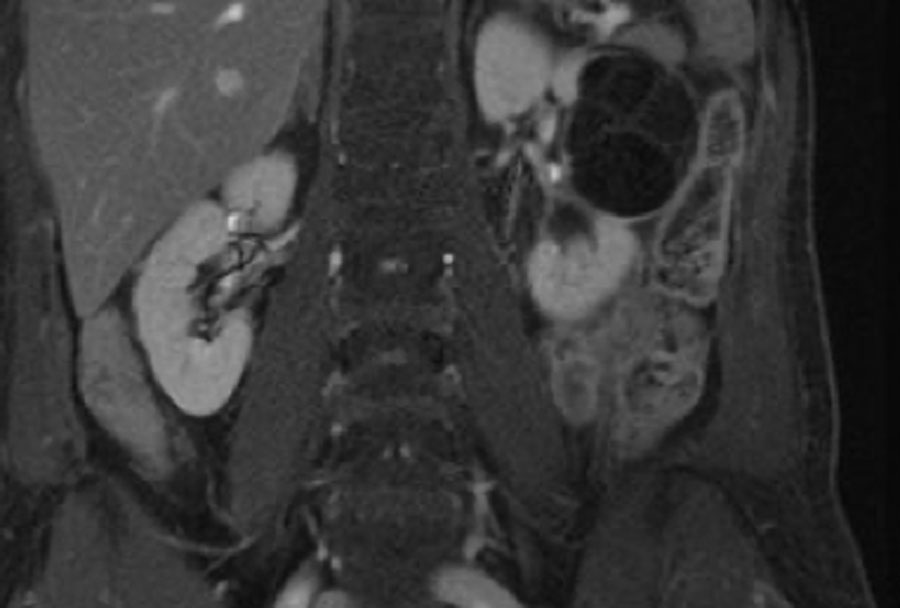

Các hình ảnh bao gồm: T2W mặt cắt ngang (axial), T1W mặt cắt coronal có kỹ thuật xóa mỡ (fatsat) và tiêm Gadolinium, và cuối cùng là T2W mặt cắt coronal.

Có một tổn thương dạng nang trong thận phải với nhiều vách ngăn mỏng (> 4 vách).

Các vách ngăn được thấy rõ hơn trên các hình ảnh mặt cắt ngang.

Các vách ngăn không có biểu hiện ngấm thuốc.

Theo phân loại cũ, tổn thương này sẽ được xếp vào nhóm IIF.

Trong phân loại cập nhật năm 2019, các vách ngăn không ngấm thuốc không được tính là vách ngăn thực sự, do đó tổn thương được hạ bậc xuống nang Bosniak II.

Nang này trước đây đã từng xuất huyết và không cho thấy bất kỳ thay đổi nào trong quá trình theo dõi suốt 5 năm.